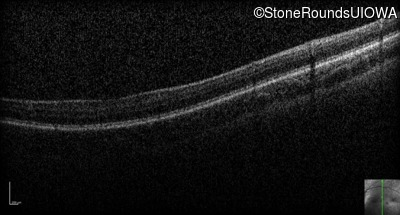

Optical Coherence Tomography - Right - 10/125

Exemplar